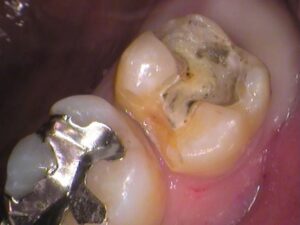

お口の中を見てみると

上の奥歯ですが、銀歯が入っています。

何年も前に虫歯治療をしたときに銀歯になったそうです。

この銀歯の中で虫歯が広がっています。

治療を始めていきます。

銀歯を削り取って外してみると、

このような状態でした。